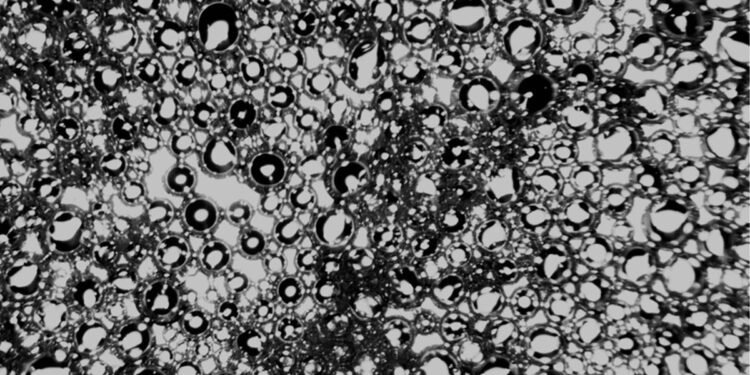

However, UCF’s invention uses nanobubbles that are sensitive to ultrasound to deliver therapy to a targeted area of the human body.

“There are many nanoplatforms for the treatment of osteoporosis,” says Razavi. “But the advantage of ultrasound-responsive nanobubbles is that they need ultrasound to destroy bubbles and transfer genes. Ultrasound itself can support bone formation.

Each nanobubble encapsulates the treatment in a gaseous core and liquid perfluorocarbon shell.

One of the advantages of nanobubbles over microbubbles is their ability to cross cell membranes to deliver therapeutic agents.